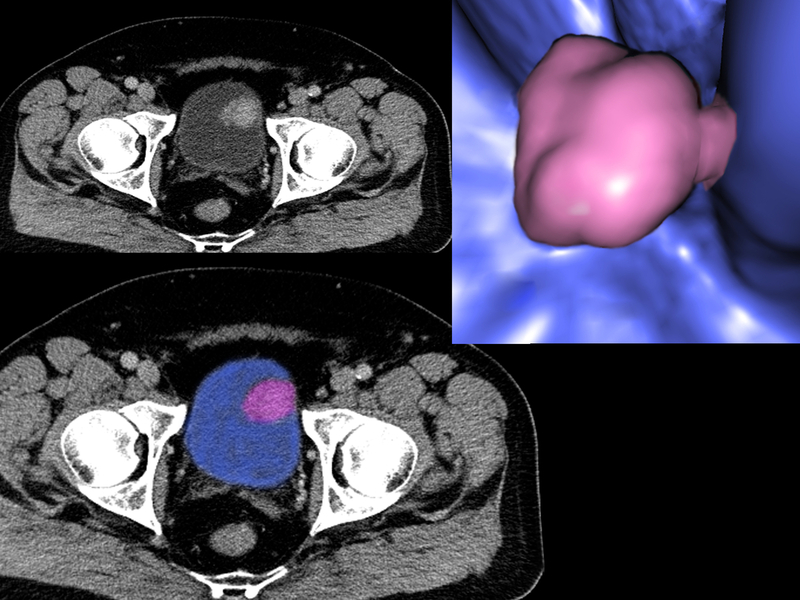

There are no approved treatment options for patients with advanced bladder cancer after they’ve received standard chemotherapy and immune treatments, but the results of a phase 2 clinical trial led by Yale Cancer Center and Smilow Cancer Hospital researchers demonstrate an effective treatment for this deadly disease. The findings were presented today at the American Society of Clinical Oncology (ASCO) Annual Meeting in Chicago, IL.

EV uses an antibody that targets a protein known as Nectin-4, expressed in high levels on the surface of urothelial tumor cells and low levels on normal cells. This antibody is chemically linked with an agent that penetrates the tumor cell and destroys its structure.